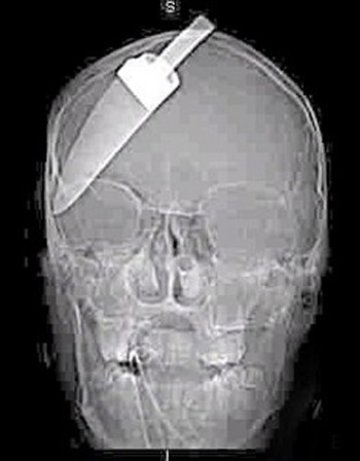

Хирурзи от клиниката към Държавния университет в Ресифе, Бразилия, извадиха 6-сантиметрово острие от черепа на 29-годишен мъж.

Морено Еделсон Маноел бил намушкан с нож в главата преди 3 г. след сбиване в бар. След инцидента веднага бил приет в местната клиника.

Лекарите обаче не поели риска да извадят острието, тъй като се страхували, че интервенцията може да бъде опасна за живота му.

Те се ограничили само с това да изпилят дръжката на ножа, която стърчала от главата му.

Острието било заседнало между мозъчните полукълба и така човекът си живял три години.

По време на операцията, в която участвали седем хирурзи, се наложило заедно с острието да бъде отстранена и част от черепа на пострадалия.